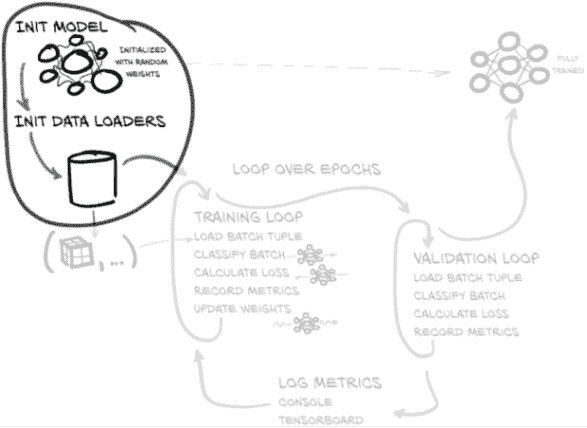

但在我们进入实验阶段之前,我们必须打下基础。让我们看看我们第 2 部分训练循环的样子,如图 11.2 所示:鉴于我们在第五章看到了一组类似的核心步骤,这应该会让人感到熟悉。在这里,我们还将使用验证集来评估我们的训练进展,如第 5.5.3 节所讨论的那样。

图 11.2 我们将在本章实现的训练和验证脚本

我们将要实现的基本结构如下:

-

初始化我们的模型和数据加载。

-

循环遍历一个半随机选择的 epoch 数。

-

循环遍历

LunaDataset返回的每个训练数据批次。 -

数据加载器工作进程在后台加载相关批次的数据。

-

将批次传入我们的分类模型以获得结果。

-

根据我们预测结果与地面真实数据之间的差异来计算我们的损失。

-

记录关于我们模型性能的指标到一个临时数据结构中。

-

通过误差的反向传播更新模型权重。

-

循环遍历每个验证数据批次(与训练循环非常相似的方式)。

-

加载相关的验证数据批次(同样,在后台工作进程中)。

-

对批次进行分类,并计算损失。

-

记录模型在验证数据上的表现信息。

-

打印出本轮的进展和性能信息。

-

当我们阅读本章的代码时,请注意我们正在生成的代码与第一部分中用于训练循环的代码之间的两个主要区别。首先,我们将在程序周围放置更多结构,因为整个项目比我们在早期章节中做的要复杂得多。没有额外的结构,代码很快就会变得混乱。对于这个项目,我们将使我们的主要训练应用程序使用许多良好封装的函数,并进一步将像数据集这样的代码分离为独立的 Python 模块。